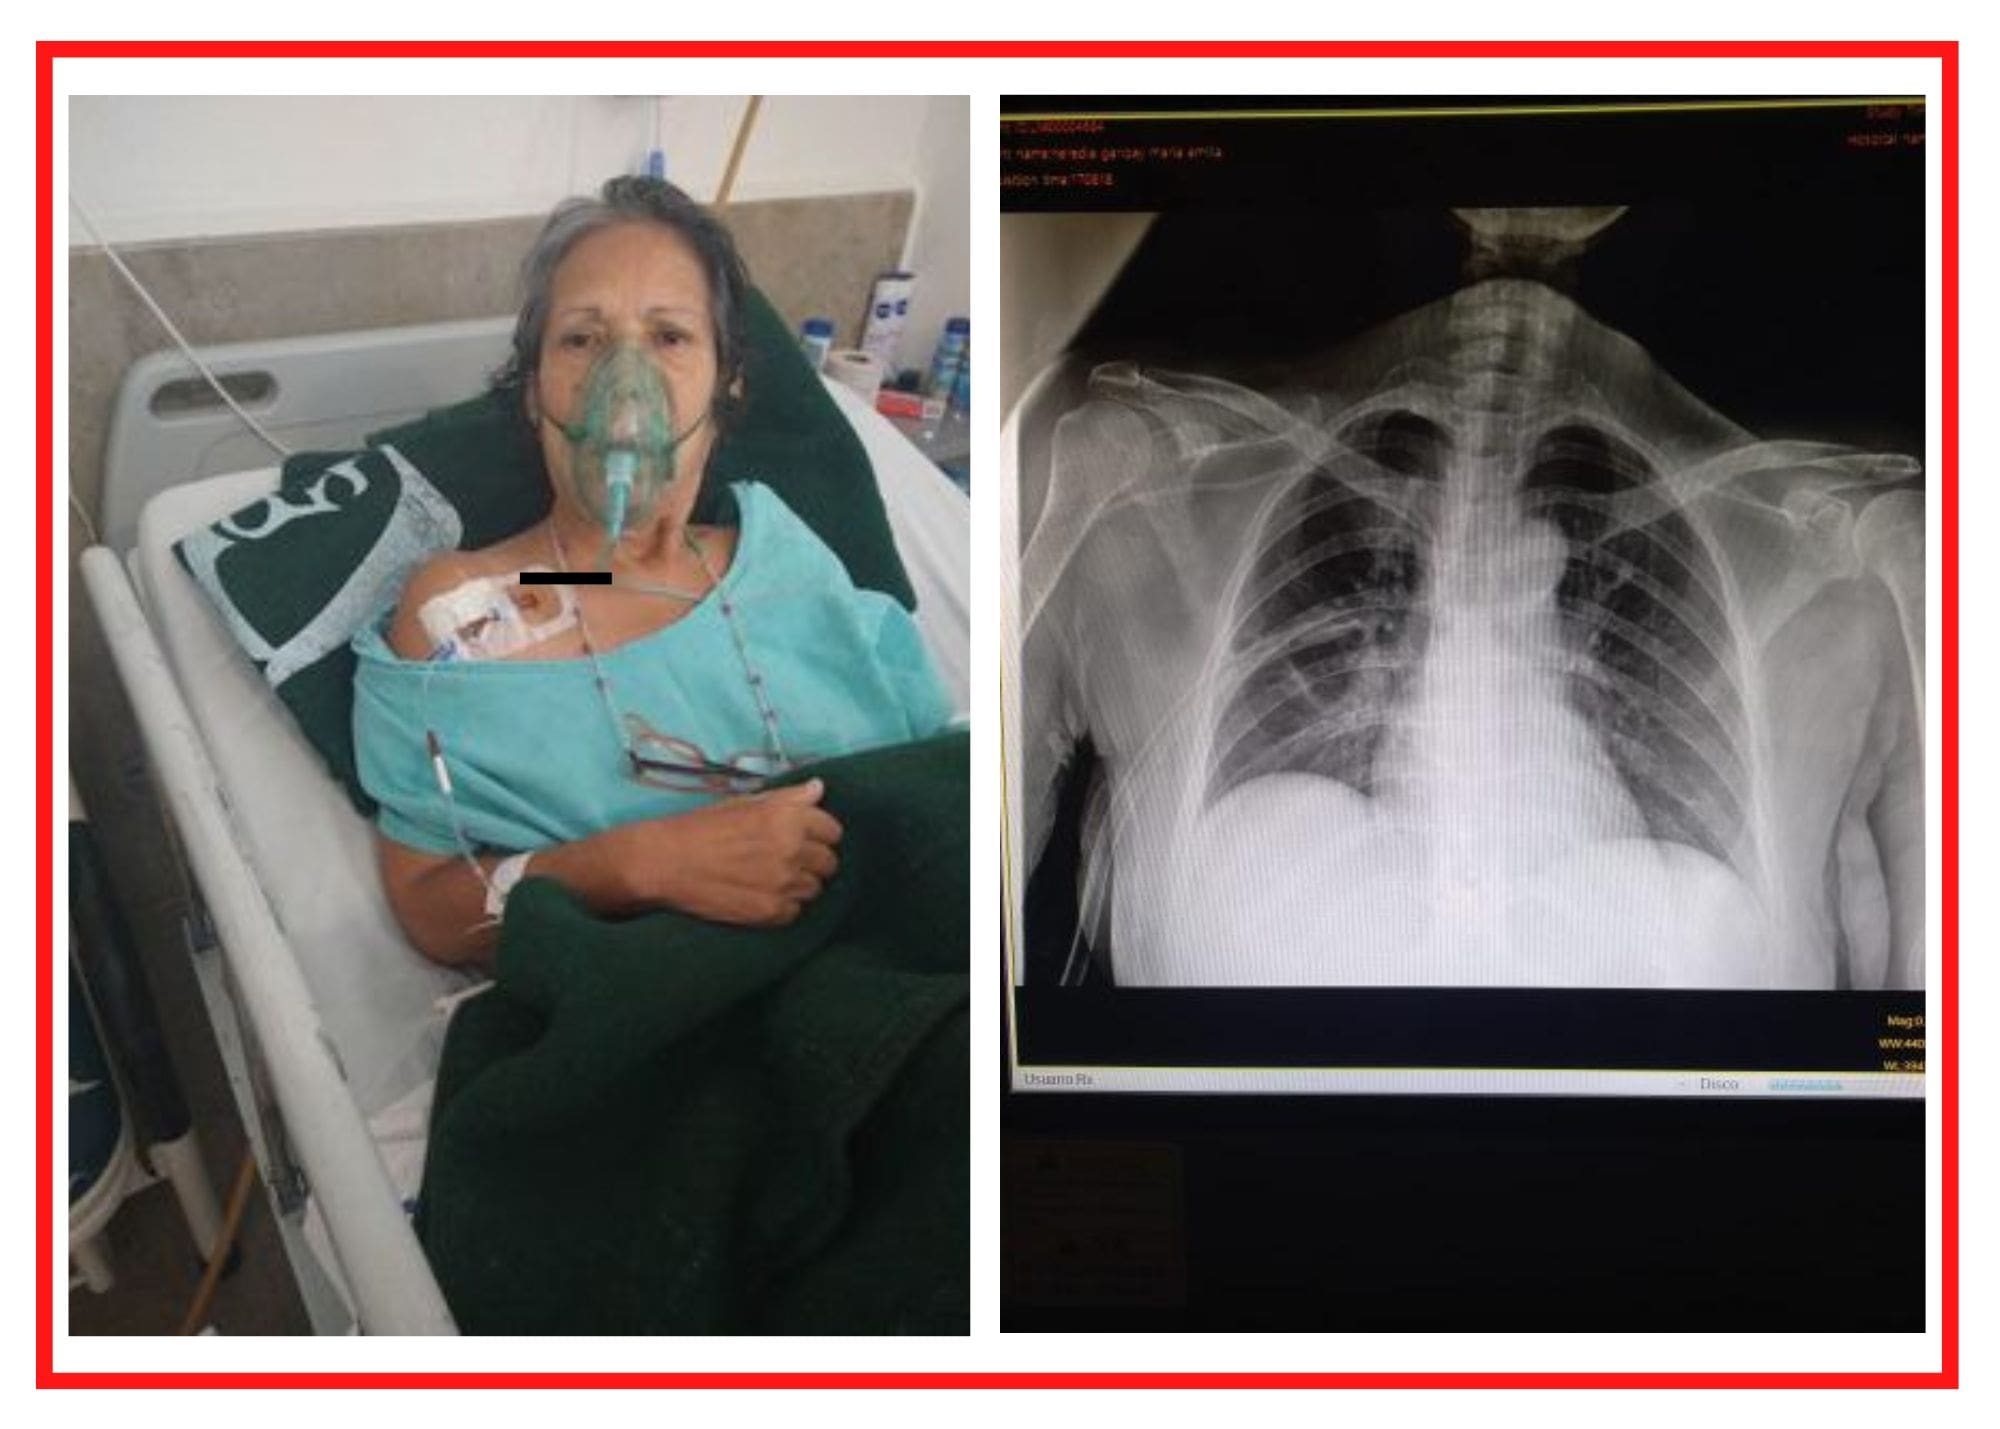

Sin embargo, durante la intervención, presuntamente la doctora Zoraida Maya Martínez le habría perforado el pulmón con uno de los instrumentos, al intentar poner un catéter, el cual debió haber colocado el anestesiólogo.

La señora sintió un dolor profundo luego de que a través de la clavícula se le perforara el pulmón.

Vio al personal médico entrar en crisis y a la doctora no actuar correctamente tras presuntamente perforarle el pulmón, a pesar que el mismo anestesiólogo le decía que la dejara de picar. La situación fue tan riesgosa que no le retiraron la vesícula y a la fecha la tiene, con el riesgo que tenga otra complicación de salud.